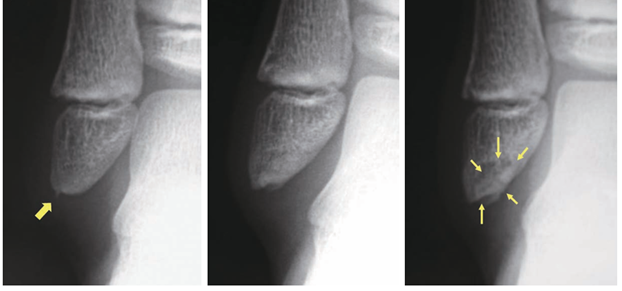

中足骨基部骨折について

黄色矢印部分に骨折線が認められています。

(図20) MB Orthop. 38(5):55—64,2025大人とこどものスポーツ外来 下肢編【こども編】小児アスリートの足関節・足部捻挫に対する外来診療 田中 博史 より抜粋

前方突起骨折について

踵骨前方突起骨折は二分靱帯の踵骨付着部の裂離骨折です。

図6・9:踵骨前方突起骨折は二分靱帯の踵骨付着部の裂離骨折である。